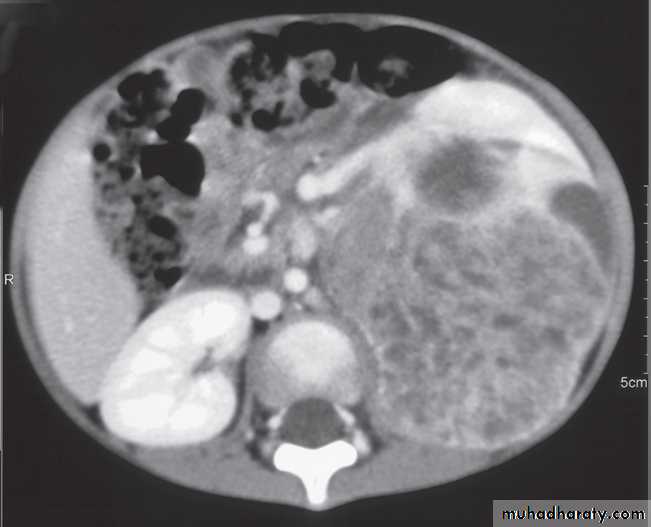

-Renal cell carcinomas are approximately spherical and often lobulated .With density similar to renal parenchyma or slightly less with often seen some areas of necrosis & calcification .

Staging of renal cell carcinoma is usually undertaken with CT, the current method of choice .

Wilms’ tumour is the likely diagnosis in a child with a renal mass. These lesions are frequently large and may contain stippled calcification